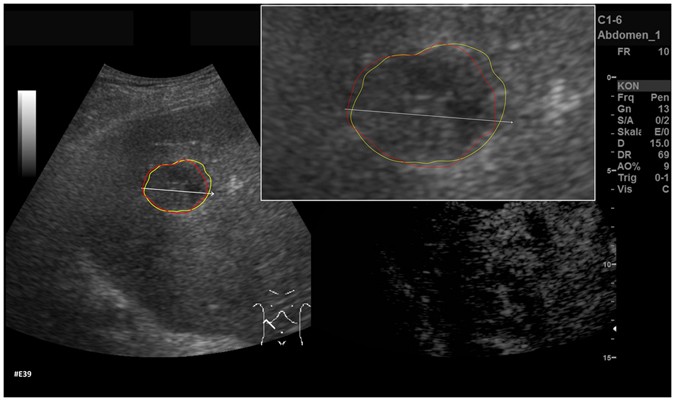

Comparison of manual and semi-automated segmentation of a pancreatic cancer liver metastasis. The native image with a zoomed view of the metastasis is presented (white box). The red outline represents the manual segmentation including the white arrow representing the manually drawn maximum diameter. The yellow line represents the result of the semi-automatic segmentation.